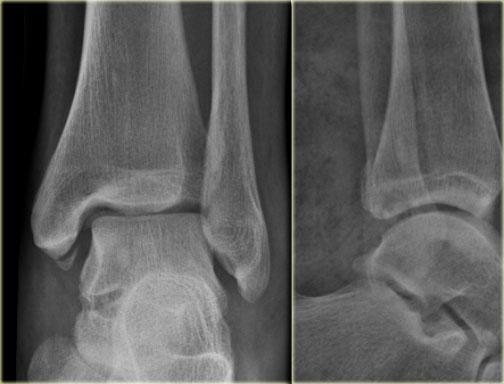

Những hình ảnh này cho thấy một gãy xương Weber B điển hình giai đoạn 4.

Có một đường gãy chéo của xương mác.

Có một gãy giật bong mắt cá sau và một gãy giật bong mắt cá trong.

Đây là một trường hợp điển hình khác của gãy xương Weber B giai đoạn 4.

Đầu tiên, hãy chú ý đến đường gãy xương mác chéo, được thấy rõ nhất trên hình chiếu nghiêng.

Đây là giai đoạn 2 và chúng ta phải giả định rằng dây chằng khớp chày mác trước đã bị đứt.

Trên hình chiếu nghiêng, có thể thấy một mảnh vỡ nhỏ của cơ mác thứ ba, cho thấy giai đoạn 3.

Bây giờ bạn bắt đầu tìm kiếm giai đoạn 4 và sẽ nhận thấy vùng thấu quang mờ ở mắt cá trong trên hình chiếu thẳng (mũi tên xanh lá).

Dựa vào hiểu biết về các giai đoạn của Lauge Hansen, đây chắc chắn phải là một đường gãy xương.